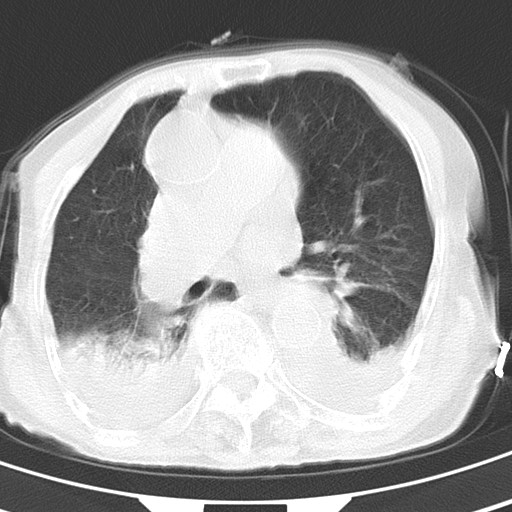

女,93岁,摔伤后检查。

右肺炎症,心功能不全伴双侧胸腔积液,右下肺膨胀不全,食管裂孔疝,冠脉钙化,心包少量积液,左侧肋骨骨折,请上传骨窗.

右侧锁骨\\肩胛骨骨折、右侧湿肺,心功能不全伴双侧胸腔积液,右下肺膨胀不全,左膈破裂或食管裂孔疝,冠脉钙化,心包少量积液,请上传骨窗.

右肺炎症,心功能不全伴双侧胸腔积液,右下肺膨胀不全,食管裂孔疝,冠脉钙化,心包少量积液,左侧肋骨骨折,右肩甲骨粉碎性骨折。93岁,高寿哇!

右肺炎症,心功能不全伴双侧胸腔积液,右下肺膨胀不全,食管裂孔疝,冠脉钙化,心包少量积液,左侧肋骨骨折,右肩甲骨粉碎性骨折。